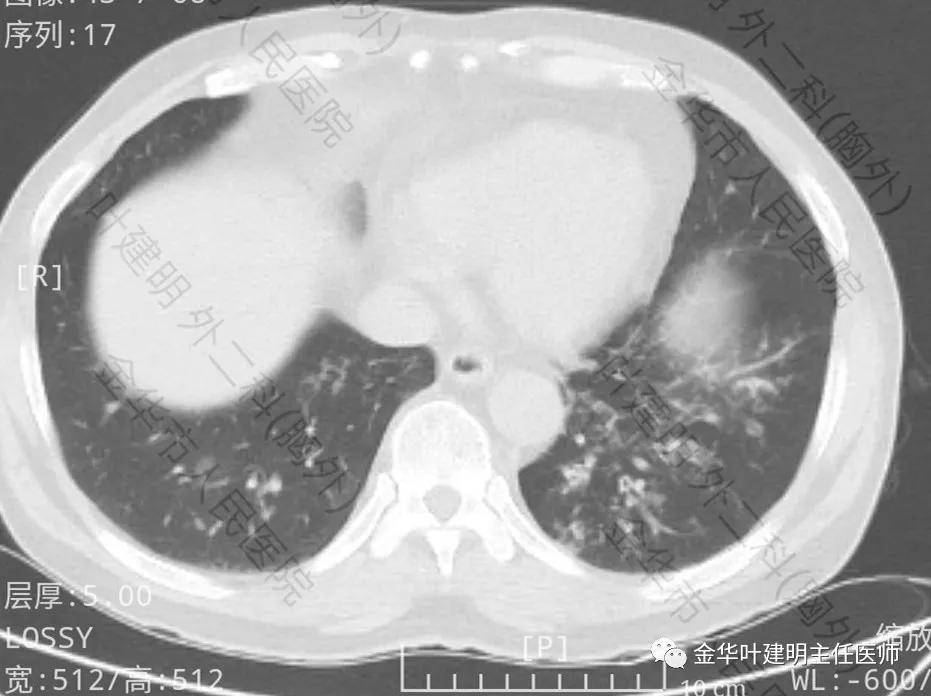

上图示左下支扩及感染